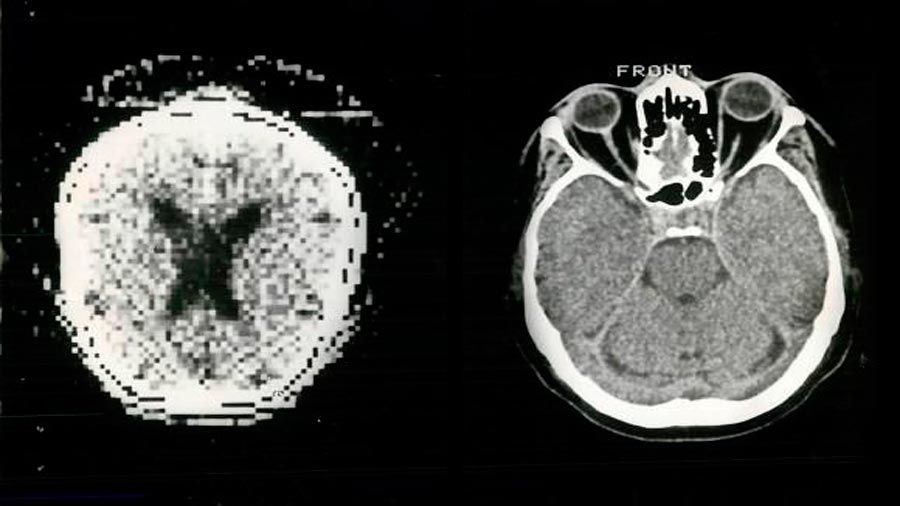

La investigación, liderada por científicos de las universidades de Notre Dame y de Wisconsin, en Estados Unidos, se contrapone a una difundida teoría que sostiene que para que un recuerdo a corto plazo pueda mantenerse, las neuronas que lo representan deben estar activas continuamente.

Para realizar el estudio, la actividad neuronal de un grupo de participantes fue analizada mientras eran expuestos a estímulos como una palabra o un rostro, según explicó a Efe Nathan Rose, uno de los investigadores.

Rose señaló que estudiaron la actividad cerebral provocada por la memoria operativa de la persona, es decir, por los procesos que intervienen en el almacenamiento temporal de la información y su posterior manipulación.

Para lograrlo, los expertos usaron un programa para identificar los patrones de la actividad cerebral causada por ese estímulo particular en la memoria operativa de cada persona.

Así notaron que cuando el participante pensaba en otra cosa, la actividad neuronal caía, como si el estímulo fuera olvidado.

Sin embargo, no era así, sino que quedaba latente a pesar de que la actividad neuronal bajara.

Al utilizar estimulación magnética transcraneal, un método no invasivo que permite inducir actividad en la corteza cerebral, los científicos pudieron recrear brevemente el recuerdo latente.

Esta reactivación sucedió y tuvo una influencia en el desempeño de la memoria solamente cuando el elemento era potencialmente relevante en el experimento, lo que para los científicos sugiere también que la representación es dinámica y modificable a través de control cognitivo.